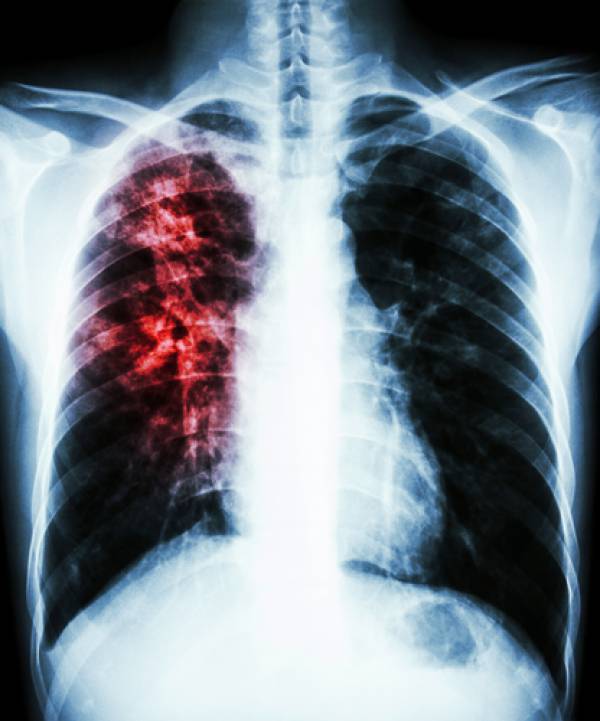

Neste período será oferecido exame de diagnóstico para esse público específico, a campanha visa também levar à populações informações sobre doença, trata-se de uma doença infecciosa e transmissível que afeta prioritariamente os pulmões, embora possa acometer outros órgãos e sistemas.

No Brasil, a doença é um sério problema da saúde pública. O principal sintoma é a tosse na forma seca ou produtiva. Por isso, recomenda-se que todo Sintomático Respiratório- pessoa com tosse por duas semanas ou mais, seja investigado.